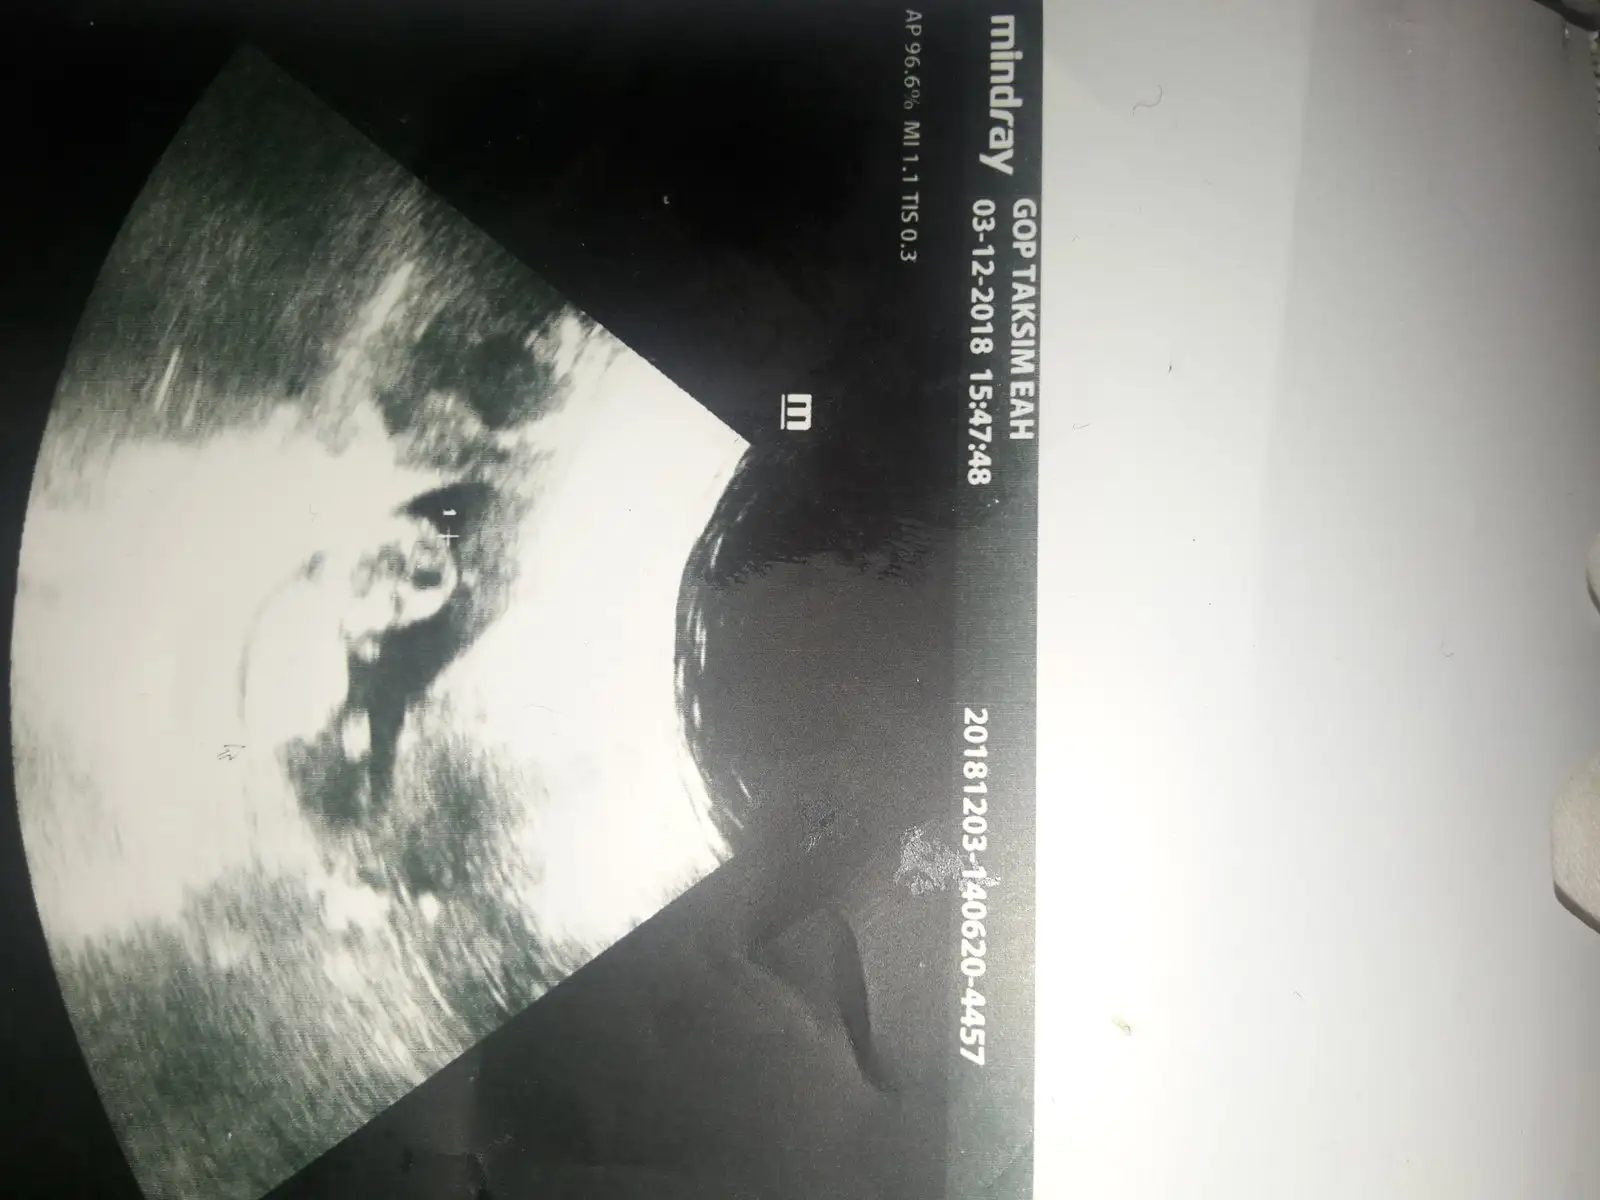

Bunu dün devlette cikarttik sizce belli mi cinsiyeti neye benziyor